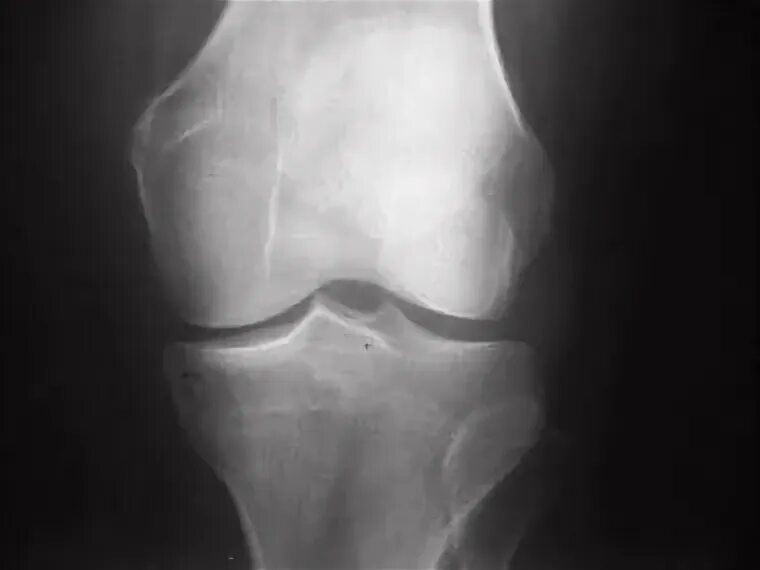

Остеофиты суставных краев